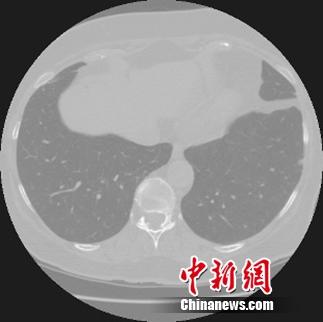

阿里云啟動天池醫(yī)療AI大賽挑戰(zhàn)早期肺癌診斷。